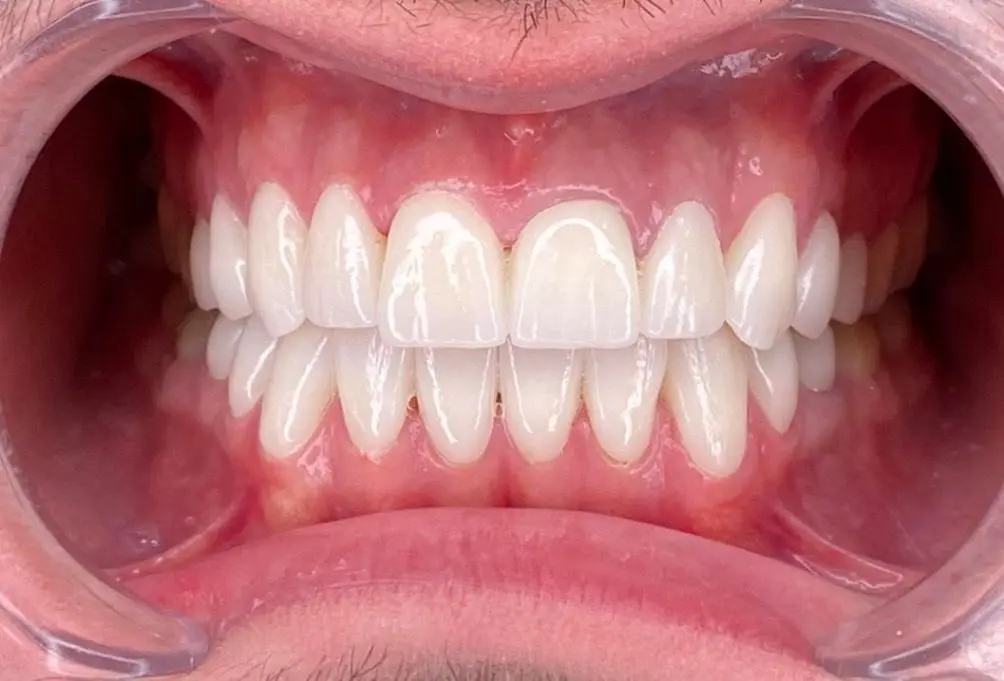

Četvrta posjeta – definitivno cementiranje

Nakon korekcije krunica i nanesene glazure krunice su dobile svoj blještavi sjaj i spremne su za definitivno cementiranje. Cementiranje se izvodi predhodno određenim redoslijedom te unešenjem cementa posebno u svaku krunicu i u konačnici stavljanjem krunice na zbrušeni zub. Zatim pristupamo uklanjanu viška cementa i čišćenju zuba kako bismo pacijentu predstavili konačni izgled “Hollywood smile” osmijeha.

Treba napomenuti da je izrada protetskog rada zajedničko djelo doktora i tehničara kao i svih ostalih kolega koji učestvuju u njegovom kreiranju. Jako je bitna komunikacija doktor-tehničar, što je ona bolja, što postoji veća doza razumijevanja, prihvatanja mišljenja i sugestija s obje strane to u konačnici rezultira maksimalnim rezultatima koje očekujemo i mi, a i sam pacijent.